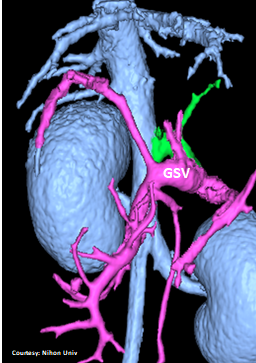

Does the GASTROSPLENIC VEIN (GSV) enter the PORTAL VEIN (PV)?

slide18